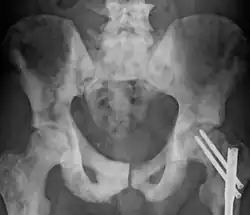

Sclerosis of the bones of the pelvis due to prostate cancer metastases

Osteosclerosis is a disorder characterized by abnormal hardening of bone and an elevation in bone density. It may predominantly affect the medullary portion and/or cortex of bone. Plain radiographs are a valuable tool for detecting and classifying osteosclerotic disorders.[1][2] It can manifest in localized or generalized osteosclerosis. Localized osteosclerosis can be caused by Legg–Calvé–Perthes disease, sickle-cell disease and osteoarthritis among others. Osteosclerosis can be classified in accordance with the causative factor into acquired and hereditary.[2][1]

Osteosclerosis can be detected with a simple radiography. There are white portions of the bone which appear due to the increased number of bone trabeculae.